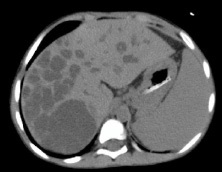

Laboratory examination showed anemia, cholestasis, hypoalbuminemia, prolonged of clotting time, elevated transaminase, elevated of gamma GT, dyslipidemia, vitamin D deficiency and positive CMV antigenemia. A doppler abdominal ultrasound was performed, which revealed intrahepatic multiple cysts, hepatomegaly with the appearance of liver fibrosis and signs of portal hypertension. From abdominal magnetic resonance imaging (MRI) with contrast showed choledochal cyst type V (according to Todani’s classification) (Figure 1) and biliary atresia (possibly type I), left kidney hypoplasia with multiple cysts, and hepatosplenomegaly.

Figure 1: Abdominal MRI with contrast.

Abdominal MRI with contrast: choledochal cyst type V (according to Todani’s classification) (figure 3) and biliary atresia (possibly type I), left kidney hypoplasia with multiple cysts, and hepatosplenomegaly.